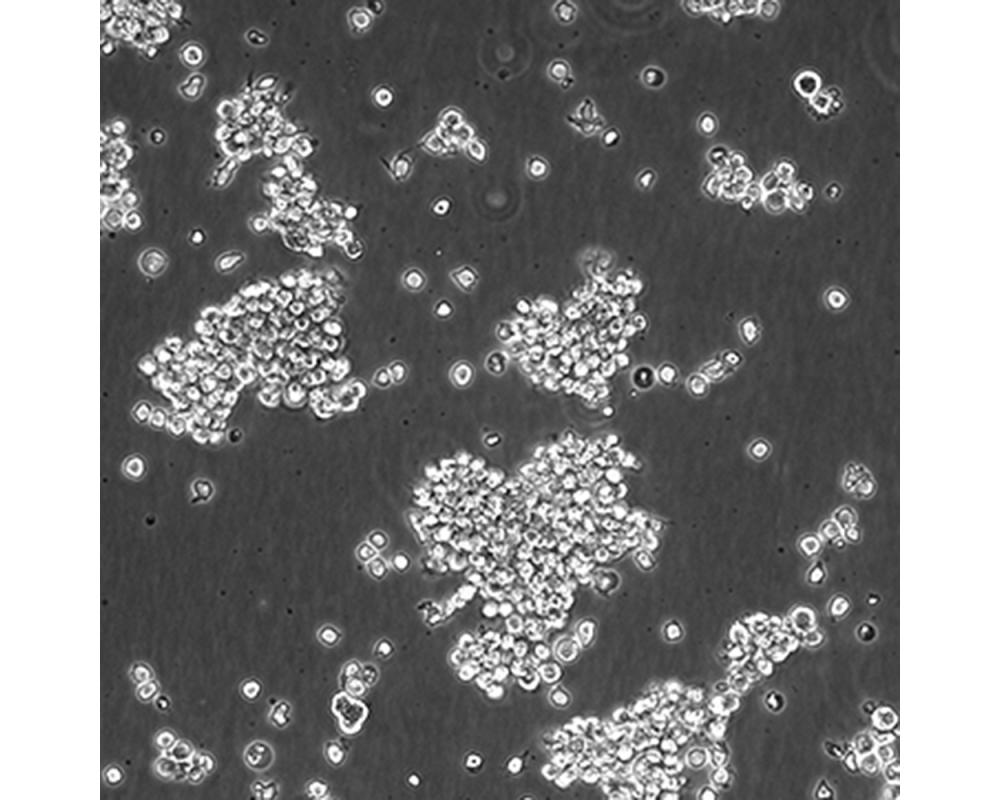

中文名稱 人間變性大細胞淋巴瘤細胞

組織來源 間變性大細胞淋巴瘤;胸腔積液轉移;女性

生長特性 懸浮

培養基 1640,90%;FBS,10%;雙抗。

傳代方法 Maintain cultures at a cell concentraion between between 1 X 10(5) and 1 X 10(6) viable cells/ml.

培養條件 Atmosphere: Air, 95%; CO2, 5%。Temperature: 37℃